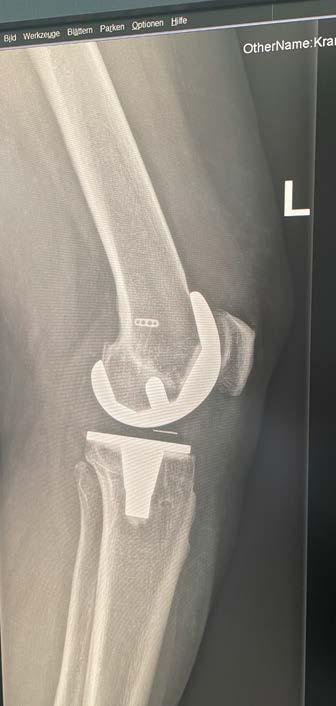

Dr. Loho: Das Kniegelenk der Patientin war schon seit längerem stark abgenutzt. Dazu kamen länger zurückliegende Verletzungen, außerdem war der Knochen sehr angegriffen. Das machte die Planung schwierig. Annemarie Kramser bekam eine Total-Endoprothese des Kniegelenks, mit dieser haben wir die Gelenkoberfläche ersetzt. Im Herz-Jesu Krankenhaus Wien setzen wir dabei auf individuell angefertigte Prothesen. Die Einzelteile werden für jede Person maßangefertigt. Ganz allgemein lässt sich sagen, dass Betroffene oft zu spät kommen. Und generell gilt: lieber früher als später mit einem schmerzenden Knie ärztlichen Rat suchen.

© Gerald Loho